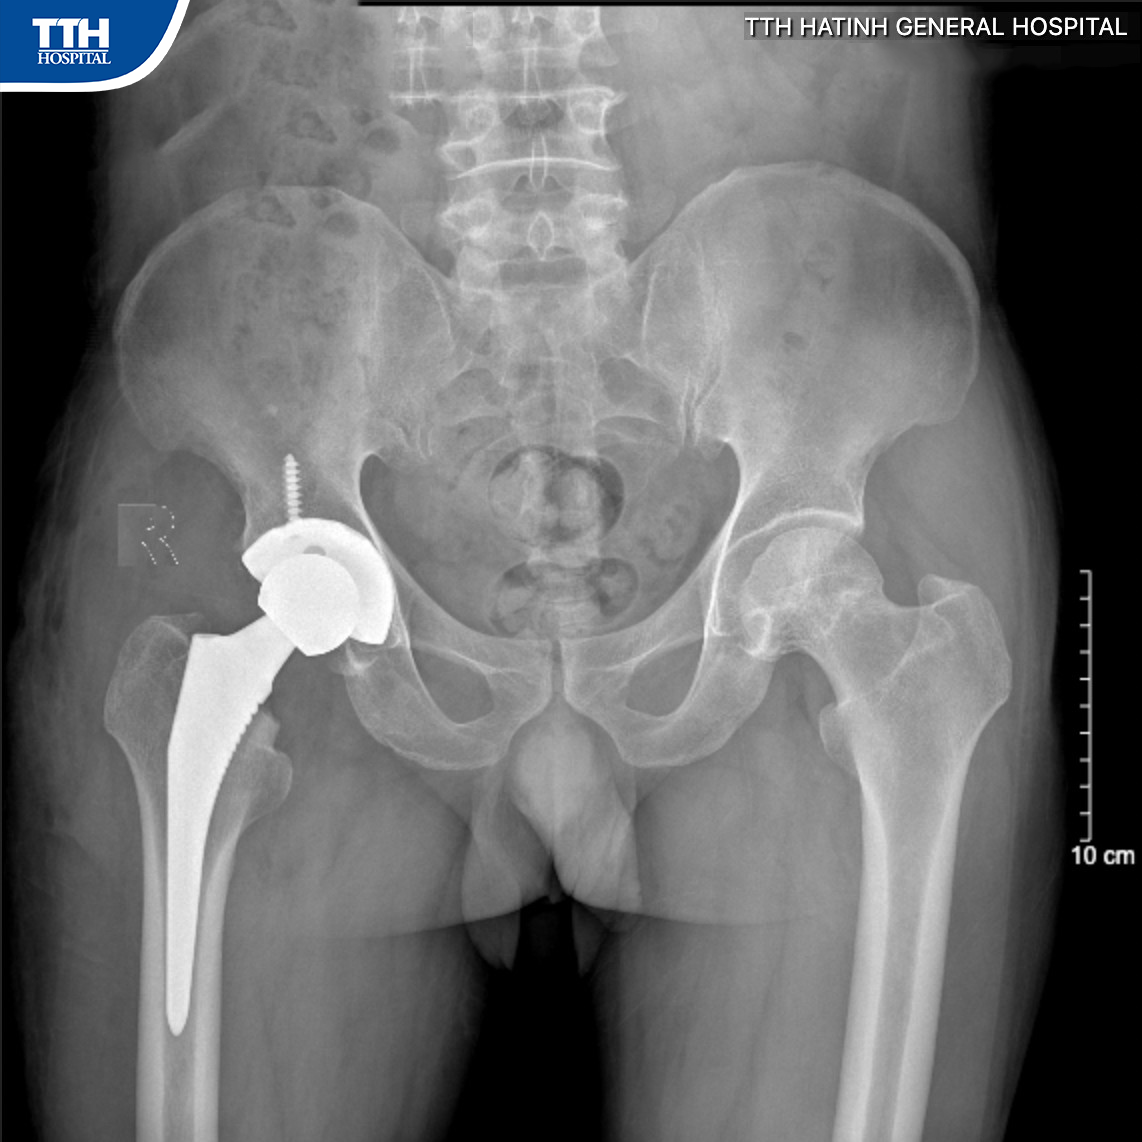

Ca phẫu thuật diễn ra thuận lợi trong khoảng 1 giờ 30’ phút. Sau phẫu thuật, người bệnh hồi phục nhanh, đứng dậy đi lại gần như bình thường từ ngày thứ 2 sau mổ. Sau 5 ngày, người bệnh có thể sinh hoạt bình thường, được phép ngồi xổm, ngồi khoanh chân cũng như ngồi bắt chéo chân và đã xuất viện’’.

Theo BSCKI Nguyễn Văn Trường – Phụ trách khoa CT - YHTT Bệnh viện Đa khoa TTH Hà Tĩnh là Bác sĩ trực tiếp phẫu thuật cho biết: ‘‘SuperPath được xem là một bước tiến vượt trội so với phương pháp phẫu thuật thay khớp háng truyền thống. Bao quanh khớp háng là nhóm cơ xoay ngoài chịu trách nhiệm giữ cho khớp háng vững chắc, không bị trật khớp trong quá trình vận động’’.

‘‘Nếu thay khớp háng theo phương pháp truyền thống thì buộc phải cắt bỏ nhóm cơ này, trong khi đó, với kỹ thuật SuperPath, Bác sĩ sẽ tiến hành bộc lộ phẫu trường và thay khớp háng mà không cần cắt cơ và bao khớp, bảo tồn được nhóm cơ xoay ngoài. Nhờ đó mà người bệnh có thể đi lại nhẹ nhàng ngay ngày đầu tiên sau phẫu thuật. Khi vết thương đã lành, người bệnh có thể thực hiện được các động tác cấm kỵ trong mổ thay khớp háng truyền thống như vắt chân chữ ngũ, ngồi xổm’’. Bác sĩ Trường cho biết thêm.